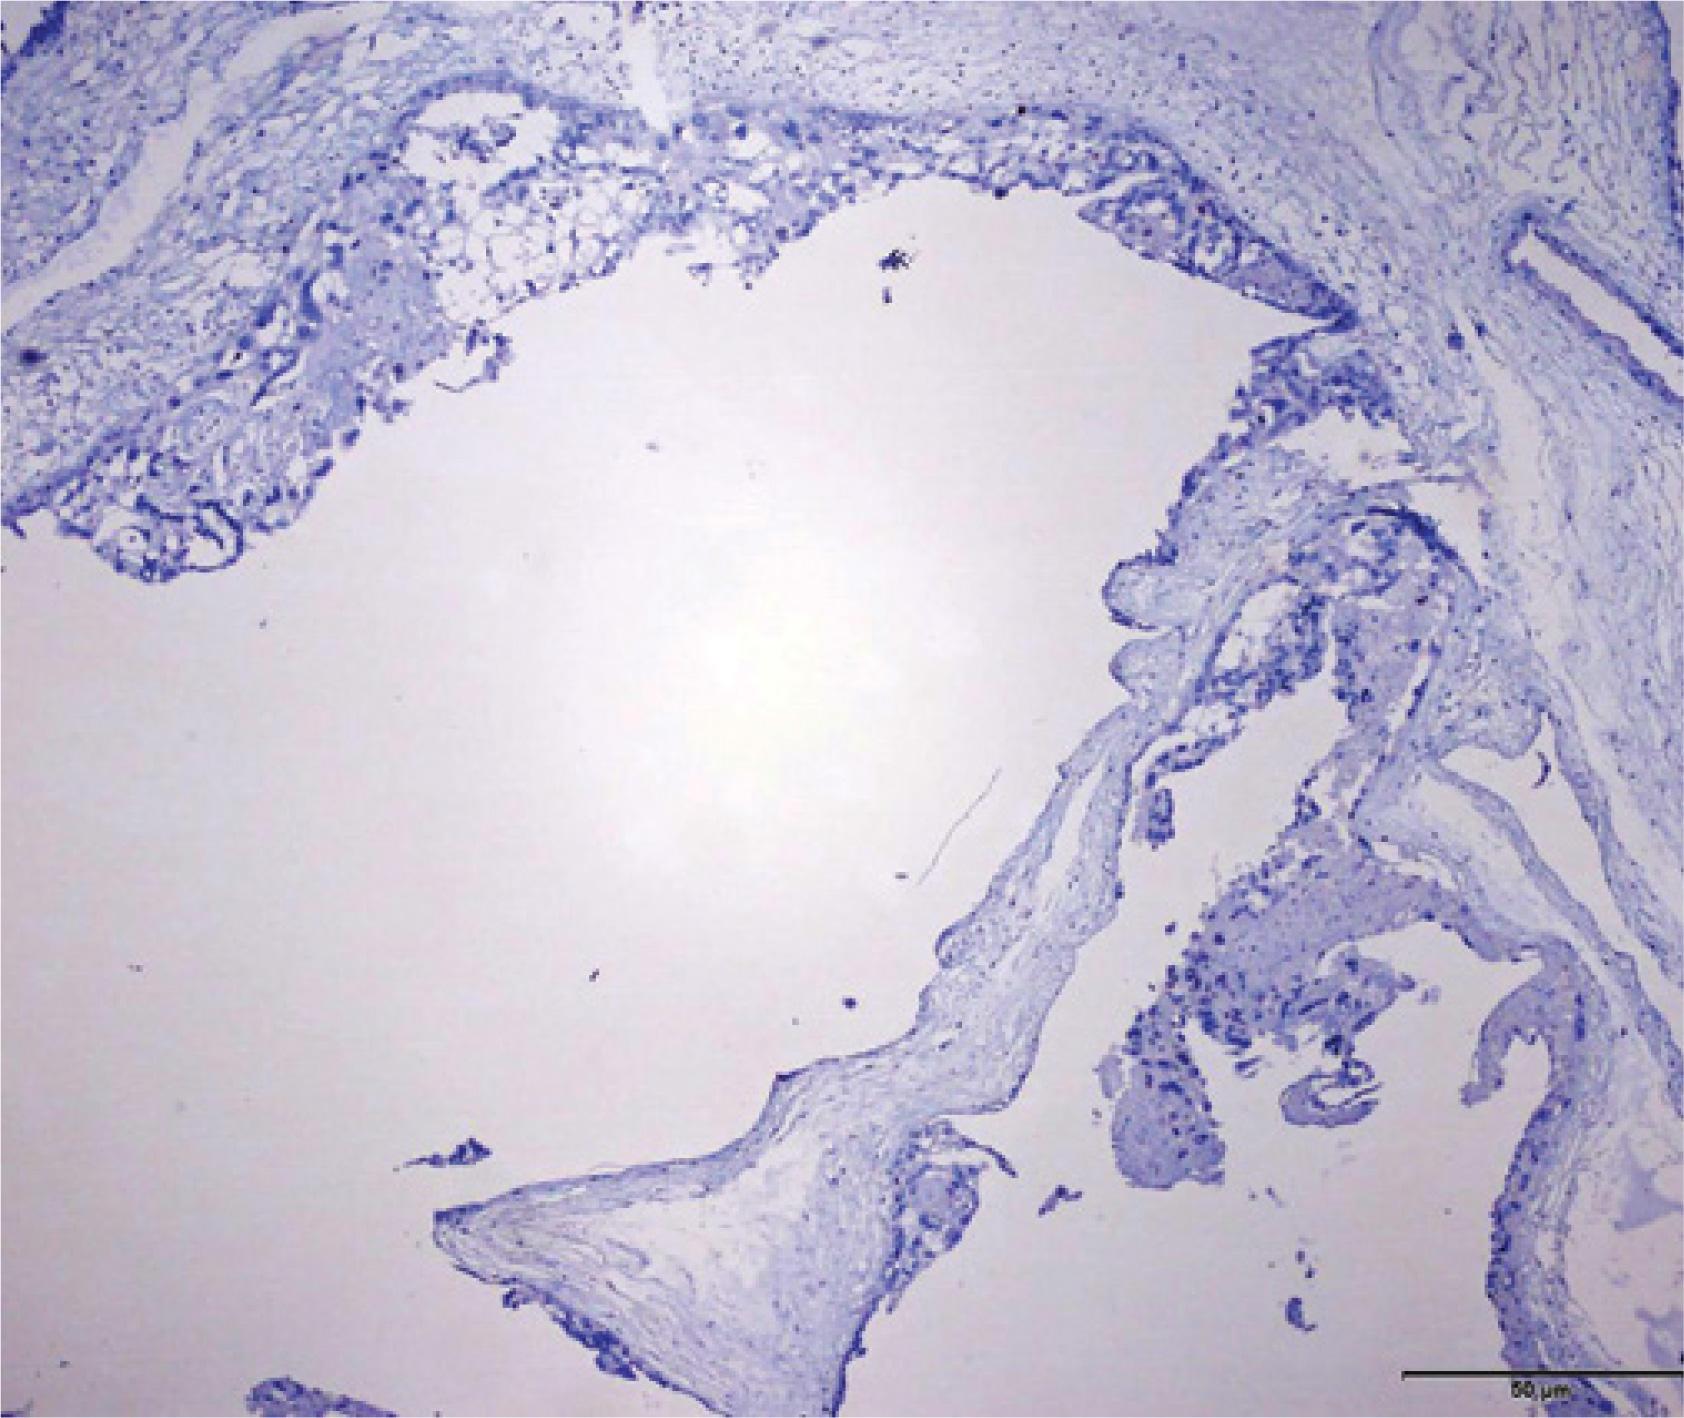

Macroscopic examination of the aspirated material showed the presence an enlarged molar mass and a male fetus (Fig. 5). The histopathology results were compatible with a second-trimester abortion and a complete hydatidiform mole, which was confirmed by p57kip2 immunohistochemistry (Neomarkers, Fremont, CA, USA), as shown in Fig. 6.

Fig. 6

Photomicrography compatible with a complete hydatidiform mole at different magnifications, compatible with a total absence of p57kip2 (Neomarkers, Fremont, CA, USA) expression in villous stromal cells and the cytotrophoblast, which are a product of diandry

Cytogenetic analysis is crucial to diagnose a twin molar pregnancy. Chorionic villus biopsy combined with amniocentesis can obtain genetic material from the suspected placenta and the fetus with a normal appearance(19). In the reported case, the sexual difference was fundamental to determine the different genetic origin of the conceptual products. For same-sex results, only the determination of the parental origin can help diagnose a complete hydatidiform mole. An interesting alternative for the evaluation of the parental genetic origin is the evaluation of the p57kip2 immunohistochemistry. The manifestation of p57kip2 is related to the genetic characterization of a paternal allele of maternal origin, and can be used in the differentiation between a complete and a partial hydatidiform mole(20). Because a complete hydatidiform mole has an androgenetic origin, maternal alleles are not present in its genetic material, and thus complete moles do not express p57kip2. We observed that the immunohistochemical analysis of the placenta was negative for p57kip2, confirming its parthenogenetic single-parent origin, diploid by karyotype, and a clear case of complete hydatidiform mole.